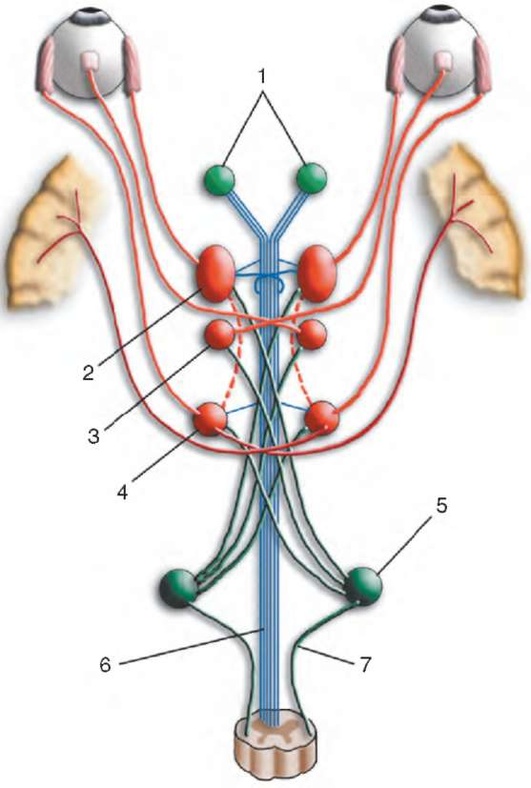

Рис. 2.1. Путь зрительных импульсов: 1 - глаз; 2 - зрительный нерв; 3 - неполный перекрест зрительных нервов (хиазма); 4 - зрительный тракт; 5 - наружное коленчатое тело; 6 - зрительная лучистость; 7 - первичная зрительная кора